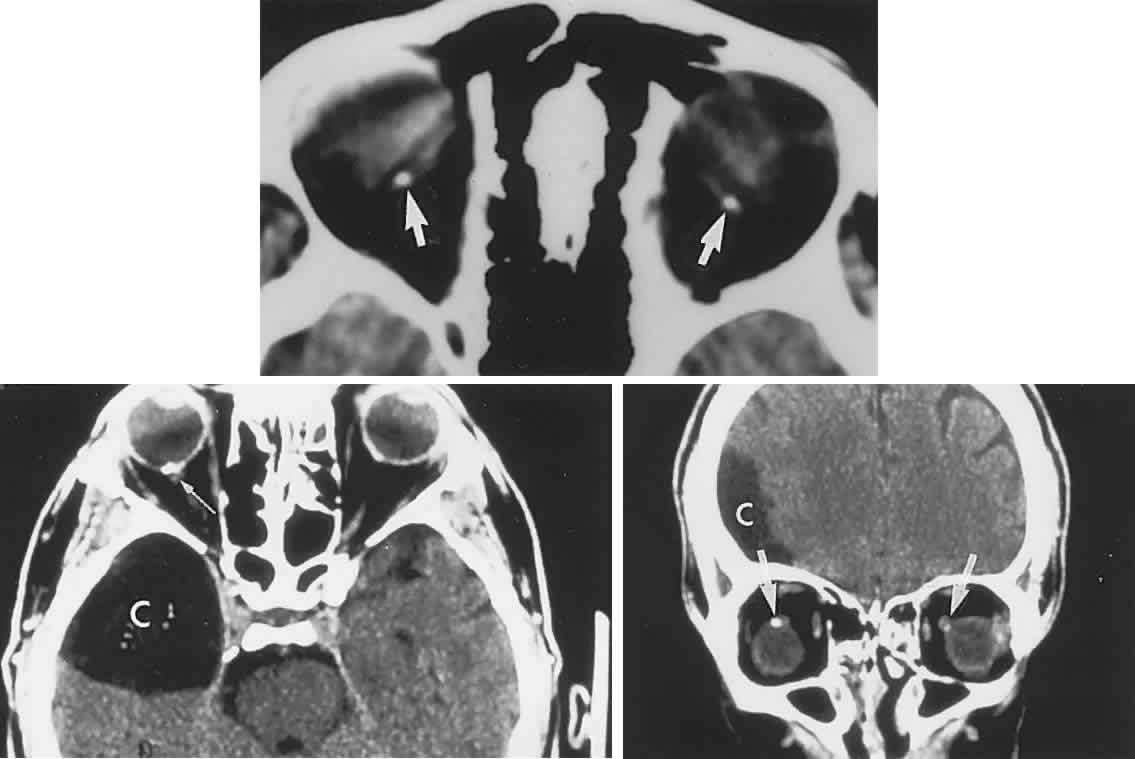

CONGENITAL HAMARTOMA SYNDROMES

The “neurophakomatoses” are a diverse group of disorders nosologically related by the presence of hamartomatous lesions, and, indeed, the term “hereditary hamartomatosis” is a more accurate description. However, whereas neurofibromatosis, tuberous sclerosis, and von Hippel-Lindau disease are transmitted with irregular dominance and considerable variation in penetrance, no hereditary basis of Sturge-Weber or angio-osteohypertrophy (Klippel-Trenaunay-Weber) syndrome has been established.

A hamartoma is a tumor of anomalous origin composed of elements normally present in the tissue in which it originates and with a limited capacity for proliferation. The following tumors may be classified as hamartomas: (1) in neurofibromatosis: optic gliomas (see Chapter 6), neurofibromas, and ganglioneuromas; (2) in tuberous sclerosis: retinal and cerebral astrocytomas, cutaneous angiofibromas (“adenoma sebaceum”), rhabdomyomas, and leiomyomas; (3) in von Hippel-Lindau disease: hemangioblastomas of the cerebellum and retina (including optic nerve head) and renal hypernephromas or cysts; (4) in Sturge-Weber disease: facial and choroidal cavernous hemangiomas and meningeal angiomatous malformations; and (5) in Klippel-Trenaunay-Weber syndrome: cutaneous nevi, visceral and limb hemangiomas, and orbitofacial venous varices.

If all disorders with neurocutaneous manifestations are considered, the term phakomatoses (Greek, phakos, “spot,” “birthmark”) is appropriate, and the catalog of “related” disorders becomes cumbersome. “The Phakomatoses,” Volume 14 of Vinken and Bruyn's Handbook of Clinical Neurology, is extraordinarily complete and serves as a source of detailed clinical descriptions of these diseases.146 Syndromes characterized by vascular hamartomas, that is, retinal-cerebellar angiomatosis (von Hippel-Lindau), and other angiomatous malformations, are discussed in Volume 2, Chapter 17.